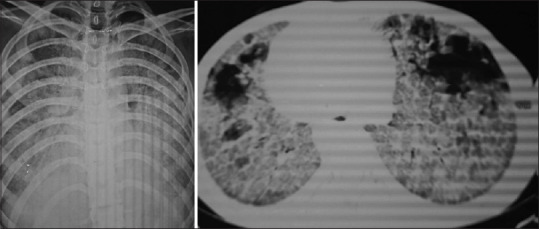

Abstract Image